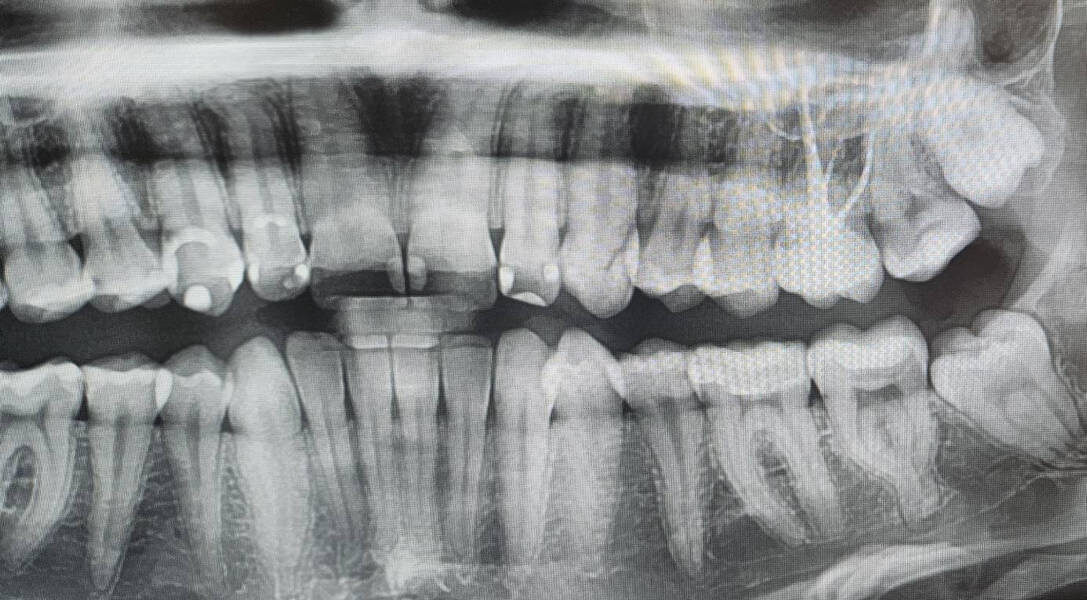

Ранее Дарья уже была на консультации в нескольких клиниках, где ей делали ортопантомографию и прицельную рентгенографию.

Ортопантомография — это рентгенологическое исследование, при котором получают панорамный снимок всех зубов, верхней и нижней челюстей, височно-нижнечелюстных суставов и части гайморовых пазух для комплексной оценки состояния полости рта.

К сожалению, на таких 2D снимках боковой канал и киста в зубе 1.6 не видны, и поставить диагноз без компьютерной томографии было невозможно😔

На рентгене видно только 3 канала, МВ2 скрыт